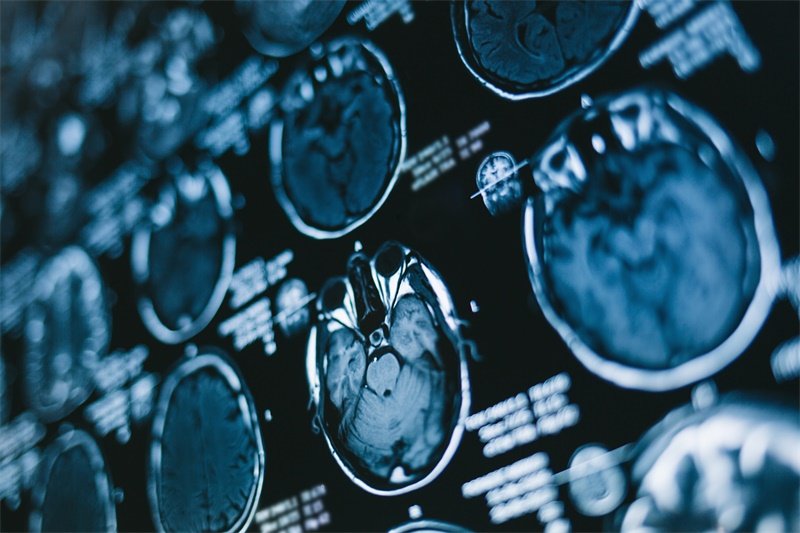

影像学检查

1. 磁共振成像(MRI):MRI 是评估脑部结构变化的最佳工具。通过高分辨率的图像,医生能够直观地查看占位的性质、大小及与周围组织的关系。

2. 计算机断层扫描(CT):CT检查虽然不如MRI精细,但能够提供关于脑出血、肿瘤等急性状况的信息。是一种快速而有效的初步评估手段。